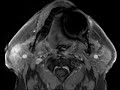

Acute parotiditis

These images show linear and diffuse areas of increased T2 signal and non-mass like enhancement predominantly involving the superficial right parotid gland, best demonstrated on fat-saturated images, as well as mild asymmetric enlargement of the gland. Findings are compatible with acute parotiditis which has a number of causes including viral or bacterial infection, sialolithiasis, autoimmune diseases, and some medications. There was no evidence of a dilated duct to suggest obstruction or atrophy of the gland on these images to suggest a chronic process.